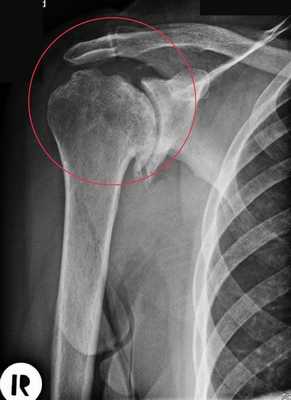

• Рентгенография обычно не позволяет адекватно оценить размеры дефекта Хилла-Сакса. На рисунке 1 показаны рентгенограммы в передне-задней (рис. 1, А) и подмышечной боковой (рис. 1, Б) проекциях пациента с рецидивирующими передними вывихами плеча: виден крупный дефект Хилла-Сакса

• На рисунке 2 представлены аксиальный (рис. 2, А) и фронтальный (рис. 2, Б) КТ-срезы пациента с рецидивирующими передними вывихами плеча. Здесь имеет место крупный сцепляющийся дефект Хилла-Сакса задневерхне-латеральной поверхности головки плеча. Обратите внимание, что этому пациенту ранее выполнялась открытая репозиция и внутренняя фиксация перелома большого бугорка—бугорок был фиксирован двумя винтами

• Трехмерная КТ-реконструкция позволяет более полно оценить размеры и локализацию дефекта и обеспечивает возможность увидеть, какая часть суставной поверхности повреждена

- Магнитно-резонансная томография (МРТ):

• МРТ позволяет оценить сопутствующие повреждения мягких тканей, а также детали костного дефекта. Аксиальные MP-сканы информативны в отношении оценки не только морфологии крупного дефекта Хилла-Сакса, но и патологии мягких тканей, сопутствующей передним вывихам плеча (рис. 3 и 4)